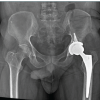

Radiographs of the hip joints revealed evident ossification(Fig. 5) and 3D-CT(Fig. 6) revealed anterior and posterior ossification around the left hip joint that suggested the diagnosis of MO. No soft tissue was visualized between the ossification and the actual femur bone around the hip. At the presentation, the level of SAP was within normal limits. The patient was consented for arthrolysis versus left total hip replacement but eventually underwent total hip replacement as excision was not possible intraoperatively (Fig. 7).

Upon recovery from the operation, the patient was able to walk independently with residual hip flexion. Postoperatively, the patient received physiotherapy and indomethacin (75 mg PO for 6 weeks) to prevent a recurrence. Follow-ups over 4 years demonstrated the full function of the affected limb and no signs of recurrence (Fig. 8).